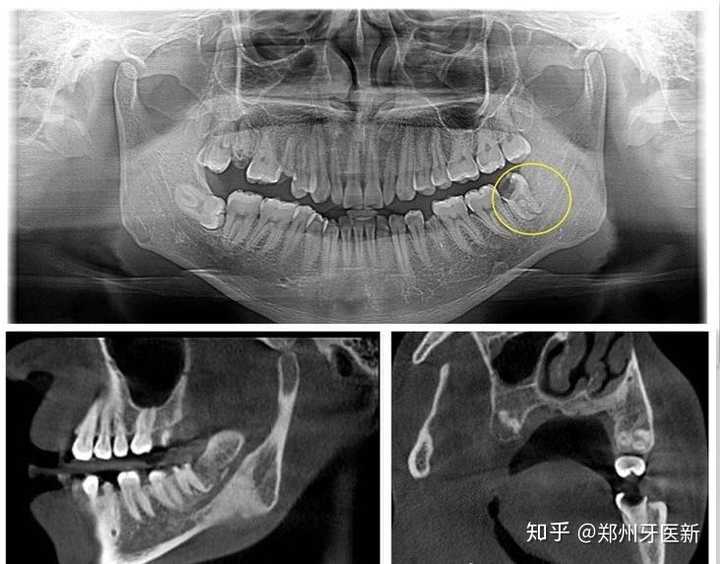

智齿ct图解析

补牙之后想要拔智齿,拍完ct后,发现红圈圈的地方疑似囊肿,建议去公立